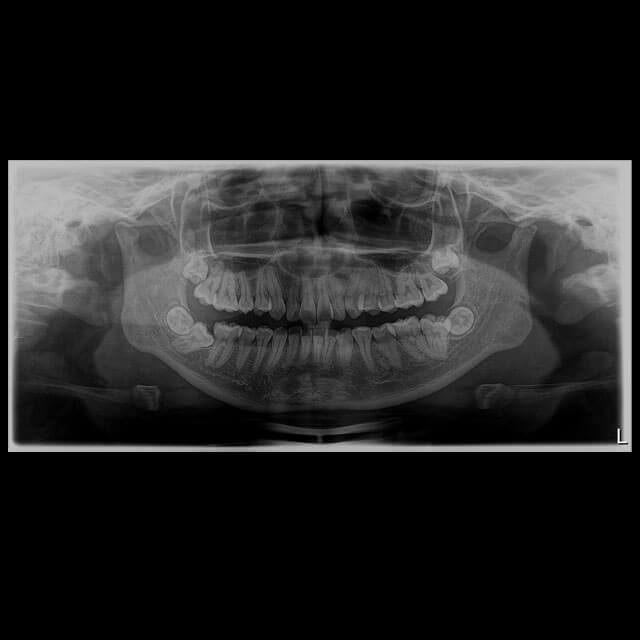

A radiografia panorâmica é uma ferramenta que permite uma exploração detalhada do complexo dento maxilar. Ou seja, permite obter uma radiografia completa da parte superior e inferior da mandíbula.

São fotografias abrangentes da face e dos dentes. Portanto, oferecem uma visão que seria invisível a olho nu.